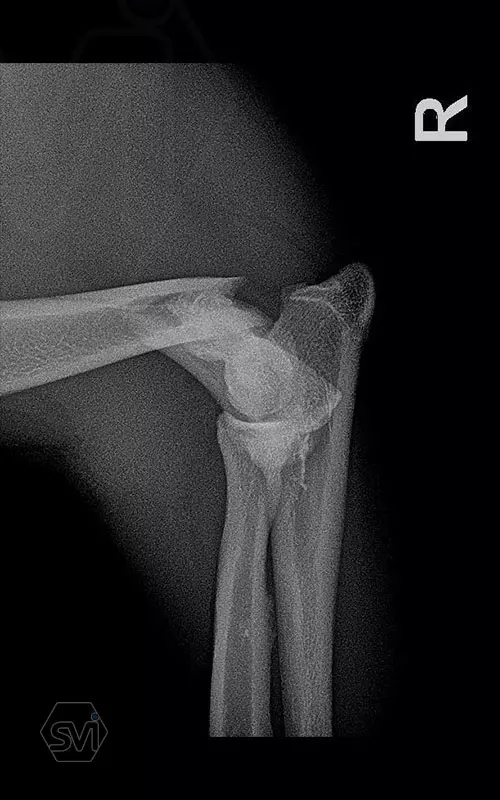

What used to be a nightmare type of surgery is slowly becoming my favorite: the humerus distal Y fracture

Yesterday, we operated on a Y fracture of the humerus of a 9-month-old French bulldog dog, where we used a cutable mini polyaxial straight plate (material thickness 2.0mm) and 2.4 polyaxial screws.

The fracture was favorable, the bone was not too fragmented, so we were able to plate the medial side easily, then turning the dog over, we replaced the lateral fragment as well and fixed it with a 2.4 intercondylar lag screw and with a shorter stright plate . It was very easy to work with the new plate, the surgery time was less than 2 hours. The stability is there, we placed a blind plug (screw head) in the lateral empty holes so that there is no weak point on the plate. The plate has mini polyax holes in which 2.4 and 2.0 polyax screws can be inserted (mini, 2.0-2.4 polyax system).

This plate arrangement and size is excellent for the treatment of the so common French bulldog humeral Y fractures.